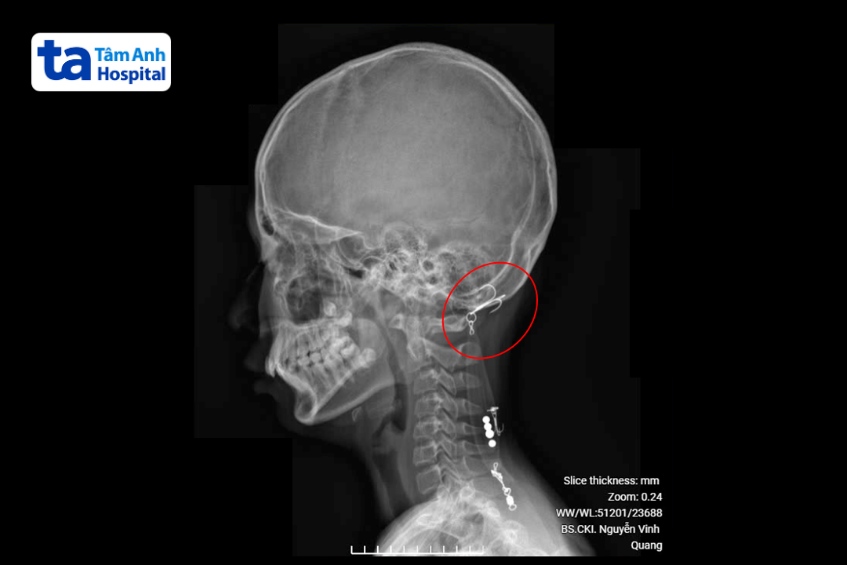

BS.CKI Lê Mạnh Hùng, khoa Cấp cứu, Phòng khám Đa khoa Tâm Anh Quận 7 cho biết bệnh nhi đến cấp cứu trong tình trạng hoảng loạn, chảy máu nhiều. Bác sĩ cầm máu, thám sát vết thương, phát hiện lưỡi câu dài khoảng 5cm đâm vào phần gáy của bệnh nhi. May mắn bé chỉ bị chấn thương phần mềm, chưa đâm vào sọ não.

Bé được gây tê, rạch một đường và lấy lưỡi câu ra, sau đó vệ sinh vết thương, khâu lại. Bệnh nhi được chỉ định tiêm ngừa uốn ván, xuất viện trong ngày.